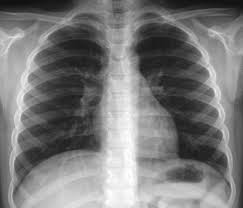

Pemeriksaan radiologik toraks merupakan pemeriksaan yang sangat penting. Kemajuan yang sangat pesat selama dasawarsa terakhir dalam teknik pemeriksaan radiologik toraks dan pengetahuan untuk menilai suatu roentgenogram toraks menyebabkan pemeriksaan toraks dengan sinar roentgen ini suatu keharusan rutin.

Pemeriksaan paru tanpa pemeriksaan roentgen saat ini dapat dianggap tidak lengkap. Suatu penyakit paru belum dapat disingkirkan dengan pasti sebelum dilakukan pemeriksaan radiologik. Selain itu,berbagai kelainan dini dalam paru juga sudah dapat dilihat dengan jelas pada foto roentgen sebelum timbul gejala-gejala klinis. Foto roentgen yang dibuat pada suatu saat tertentu dapat merupakan dokumen yang abadi dari penyakit seorang penderita, dan setiap waktu dapat dipergunakan dan diperbandingkan dengan foto yang dibuat pada saat- saat lain.

Photo Toraxs

V. INTERPRETASI FOTO THORAX

Cara sistematis untuk membaca foto thorax, sebagai berikut :

1.     Cek apakah sentrasi foto sudah benar dan foto dibuat pada waktu inspirasi penuh. Foto yang dibuat pada waktu ekspirasi bisa menimbulkan keraguan karena bisa menyerupai suatu penyakit misal kongesti paru, kardiomegali atau mediastinum yang lebar. Kesampingkan bayangan-bayangan yang terjadi karena rambut, pakaian atau lesi kulit.

2.    Cek apakah Exposure sudah benar ( bila sudah diperoleh densitas yang benar, maka jari yang diletakkan di belakang “daerah yang hitam” pada foto tepat dapat terlihat). Foto yang pucat karena “underexposed” harus diinterpretasikan dengan hati-hati, gambaran paru bisa memberi kesan adanya edema paru atau konsolidasi. Foto yang hitam karena “overexposed” bisa memberi kesan adanya emfisema.

3.    Cek apakah tulang-tulang (iga, clavicula, scapula,dll) Normal.

5.    Cek apakah posisi diafragma normal ; diafragma kanan biasanya 2,5 cm lebih tinggi daripada kiri. Normalnya pertengahan costae 6 depan memotong pada pertengahan hemidiafragma kanan.

6.    Cek sinus costophrenicus baik pada foto PA maupun lateral.

7.    Cek mediastinum superior apakah melebar, atau adakah massa abnormal, dan carilah trachea.

8.    Cek adakah kelainan pada jantung dan pembuluh darah besar. Diameter jantung pada orang dewasa (posisi berdiri) harus kurang dari separuh lebar dada. Atau dapat menentukan CTR (Cardio Thoracalis Ratio).

9.    Cek hilus dan bronkovaskular pattern. Hilus adalah bagian tengah pada paru dimana tempat masuknya pembuluh darah, bronkus, syaraf dan pembuluh limfe. Hilus kiri normal lebih tinggi daripada hilus kanan.